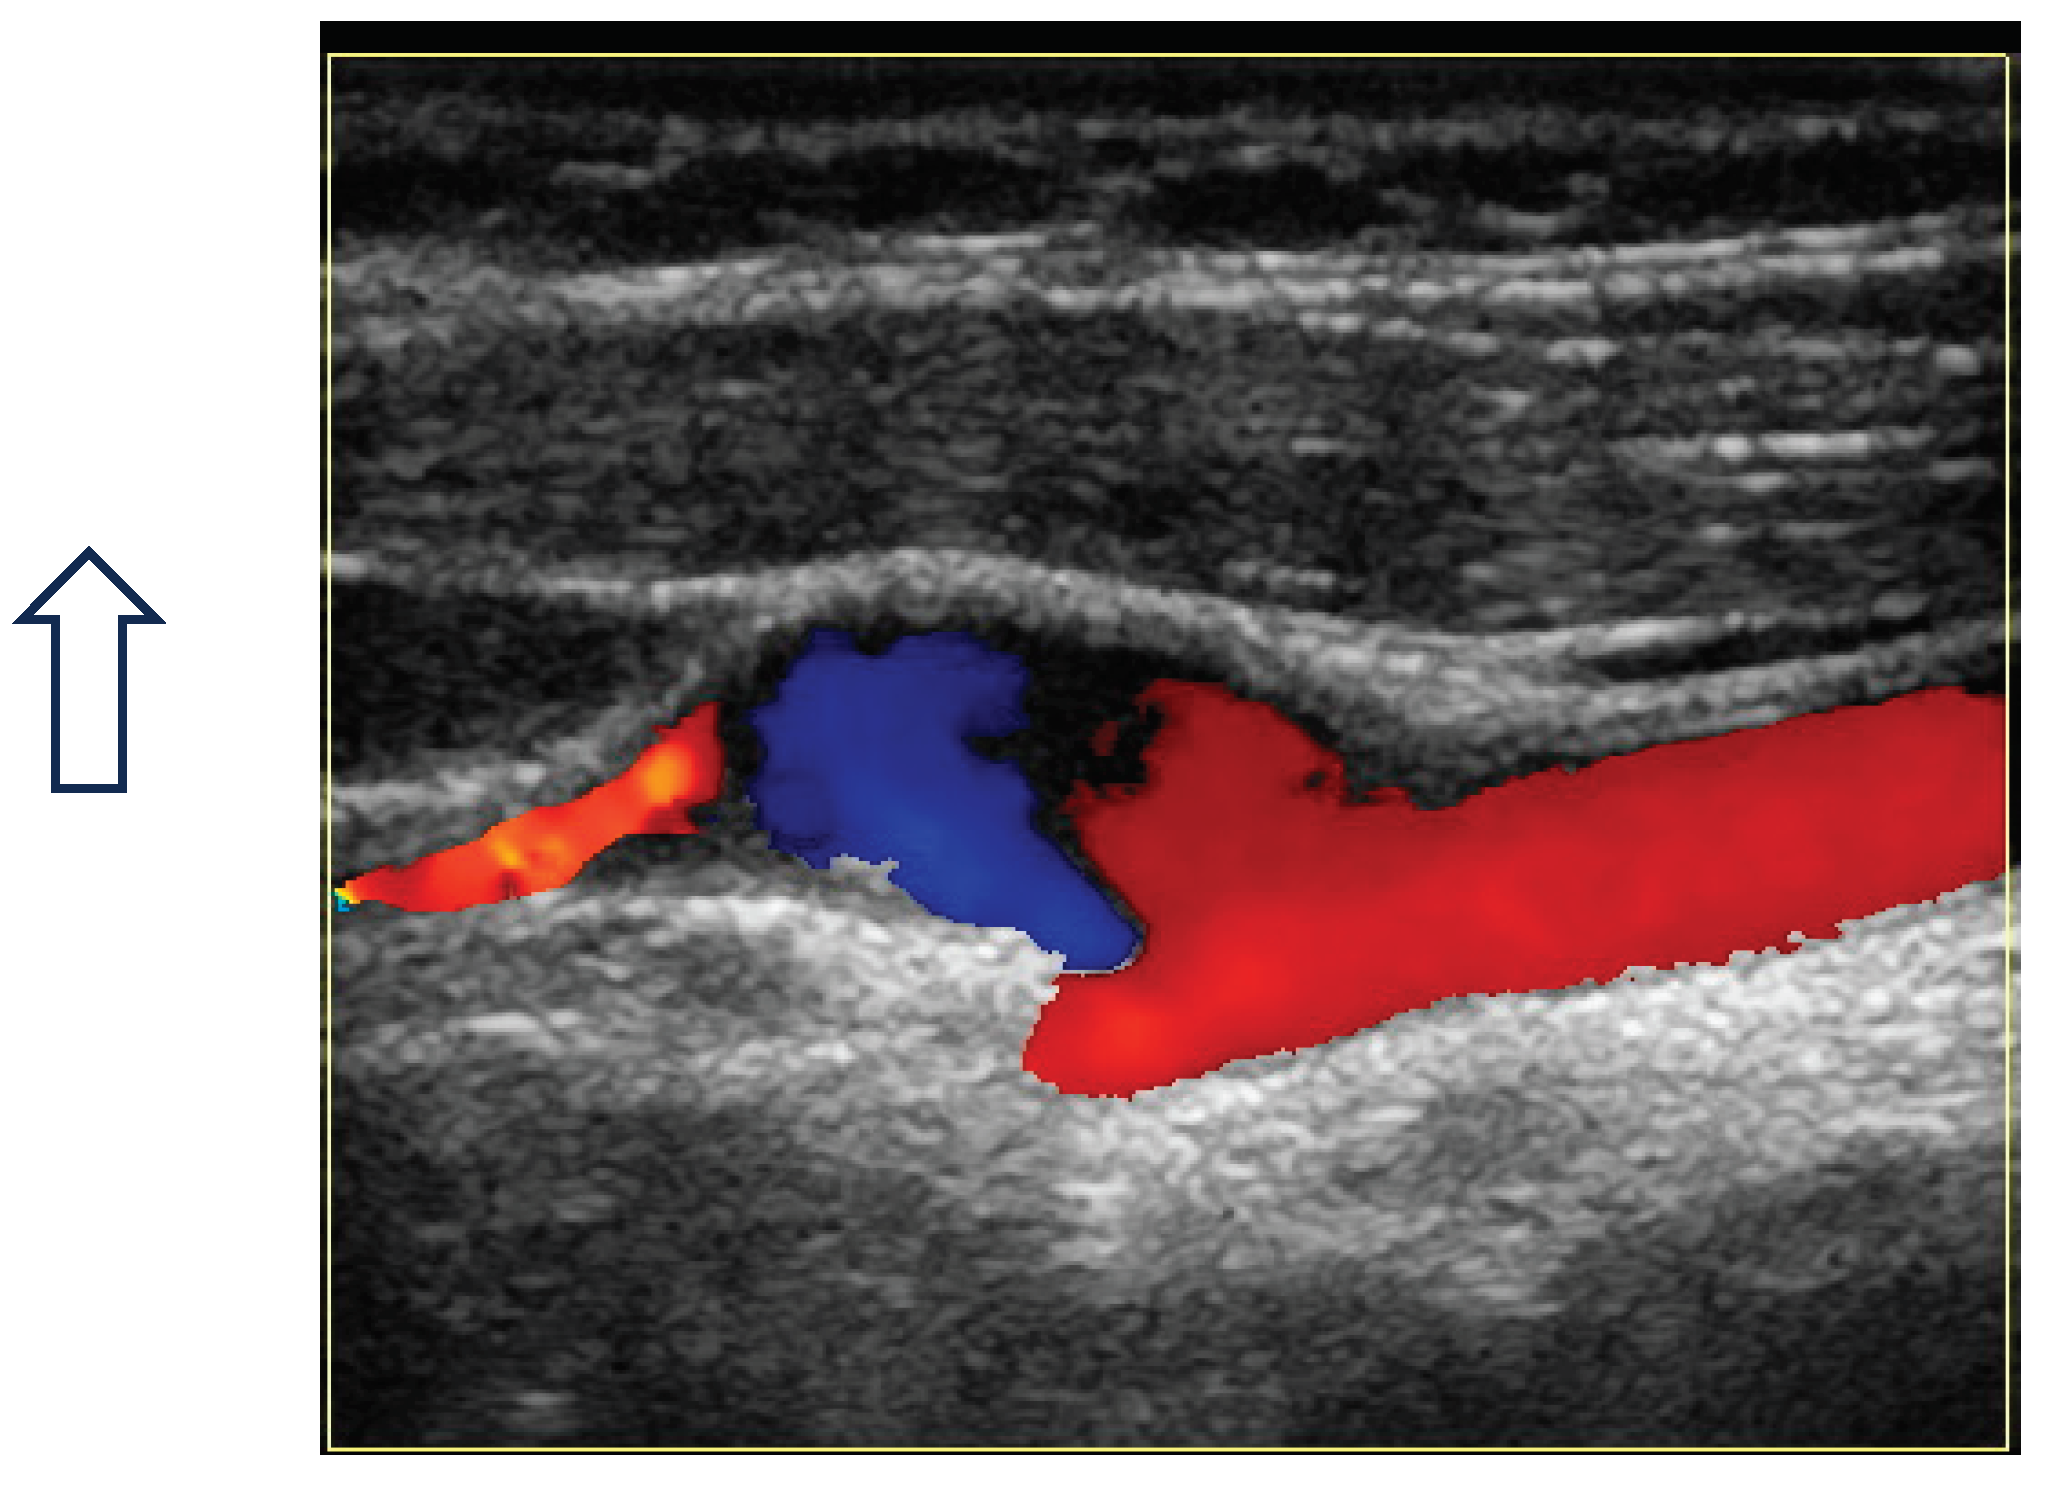

Since the advent of endovascular procedures, the histopathological classification has been replaced by an angiographic classification: focal or multifocal FMD. Multifocal FMD alternates areas of stenosis and dilation (“string of beads”) and is usually located in the mid and distal portion of the artery [147,148]. Recently, aneurysm, dissection, and arterial tortuosity have been included in the phenotype of FMD. However, a diagnosis of FAD cannot be established in the absence of focal or multifocal stenosis. Tortuosities can also be seen in the carotid, vertebral, and renal arteries. Tortuosity of the mid to distal portion of the internal carotid artery (ICA) may lead to an “S-curve”. The S curve is not specific for FMD, but its presence in individuals <70 years of age should alert the clinician [147]. Figure 1 and Figure 2.

Headaches are the most frequent, but non-specific symptoms (50-70% of patients with FMD) [147,151]. Pulsatile tintinnus may be associated with cervical artery dissection. The prevalence of cervical artery dissection and intracranial saccular aneurysm is higher among patients with FMD, with a higher rate of neurological complications (TIA, ischemic stroke, subarachnoid hemorrhage). Figure 3

The risk of long-term progression of FMD and the occurrence of aneurysm and dissection are not well-known [148]. CTA and MRA are the initial imaging modalities. Catheter-based angiography must be reserved for cases that may require intervention. Carotid DUS maybe useful for surveillance, but with some drawbacks: unsatisfactory access to vertebral and carotid arteries (especially the distal cervical portion of the ICA and intracranial arteries), no validated criteria for FMD [147]. Figure 4 and Figure 5